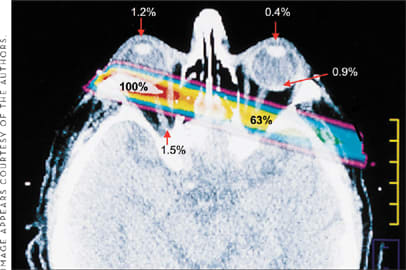

Collectively, these trials have led to equivocal or less effective therapy than current market agents. Why have these trials failed to show statistically significant efficacy outcomes? As depicted in the Figure by Marcus et al., the linear accelerator, such as that typically used in the above-mentioned studies, projects a wide beam across ipsilateral and contralateral critical structures, with 63% of the dose being delivered to the contralateral brain, 1.5% to the ipsilateral optic nerve, and 1.2% to the ipsilateral lens.16 Due to this imprecision, only a small amount of radiation was applied at each setting.

Figure. Radiation distribution using a linear accelerator for AMD therapy.

Therefore, the previous external beam studies have a major drawback: The radiation delivered to the macula was limited by technical inability to precisely localize energy on target. Consequently, small doses were given over a longer period of time (fractionation). No data support the assertion that radiation fractions are indeed cumulative in biologic effect on CNV (ie, that 8 doses of 2 Gy are equivalent to a single 16 Gy dose). Furthermore, the patients' eyes were not mapped in space relative to the X-ray beam and were not immobilized throughout treatment. Thus, confirmation and stability of beam targeting during the therapeutic fraction were not achieved, and fixed-beam, high-energy devices directed radiation across critical structures, such as the lens, the ciliary bodies, and the optic nerve.